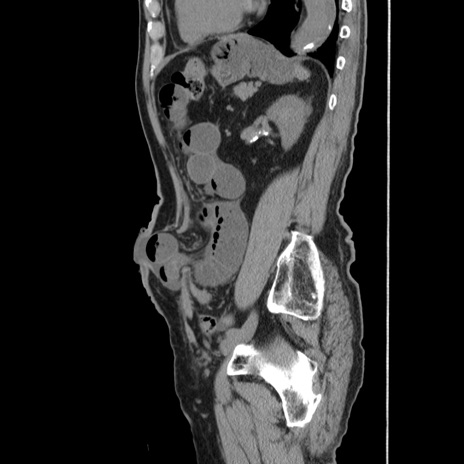

症例24(矢状断像)

【症例】80歳代男性

【主訴】左側腹部痛、嘔吐

【現病歴】本日早朝より左腹部に痛みあり。昼頃嘔吐認めたため、救急要請。

【既往歴】直腸癌(Mile手術)、胆摘

【身体所見】意識清明、BT 35.9℃、BP 221/93mmHg、SpO2 97%(RA) 、腹部:左ストーマ周囲に限局性の腹部膨隆あり。 膨隆部自発痛・圧痛あり・軟。

【データ】WBC 7700、CRP 0.09